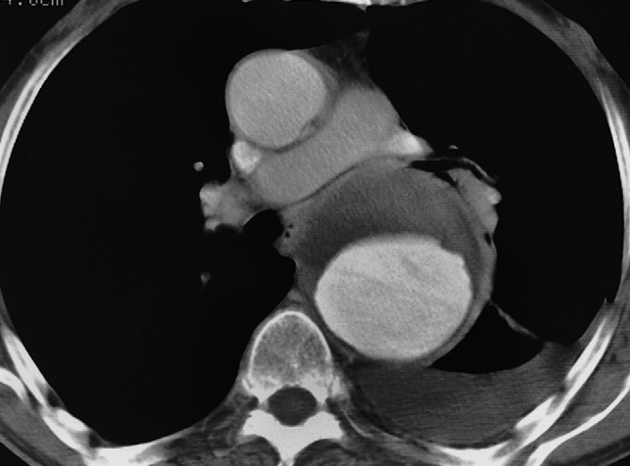

CT Chest Axial window – aortic dissection – Aneurysm diltation.